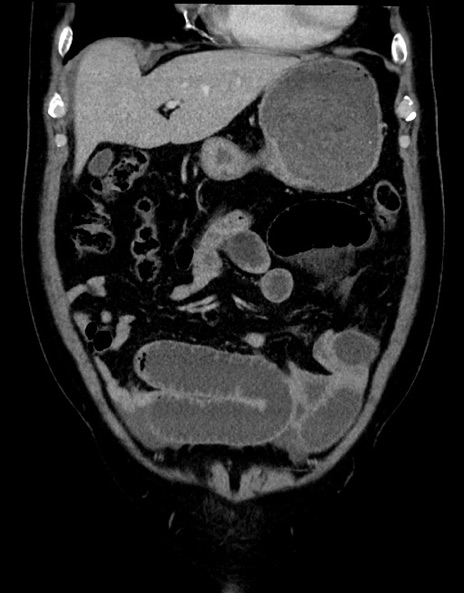

横断像

【症例】70歳代男性

【主訴】腹痛

【現病歴】今朝から腹痛あり。全体的に痛い。特に左上の方。排ガスが今日はない。冷や汗が出る。

【既往歴】直腸癌術後

【身体所見】左側腹部〜上腹部に圧痛あり。腹膜刺激症状明らかなではない。軽度反跳痛。左下腹部に術後瘢痕あり。

【データ】WBC 7700、CRP 0.02